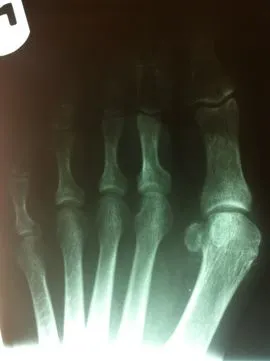

Before and immediately postop S/P bunionectomy

Pre and Postop Xrays

X-rays demonstrating correction of bunion deformity with the great toe deviated laterally (left image) and notice the position of the sesamoid bones which are the small round bones near the joint. The post-surgical film (right image) depicts alignment of the great toe significantly improved and the position of the sesamoid is underneath the 1st metatarsal head where it should be. This is a case where two surgical screws were used to fixate the correction.